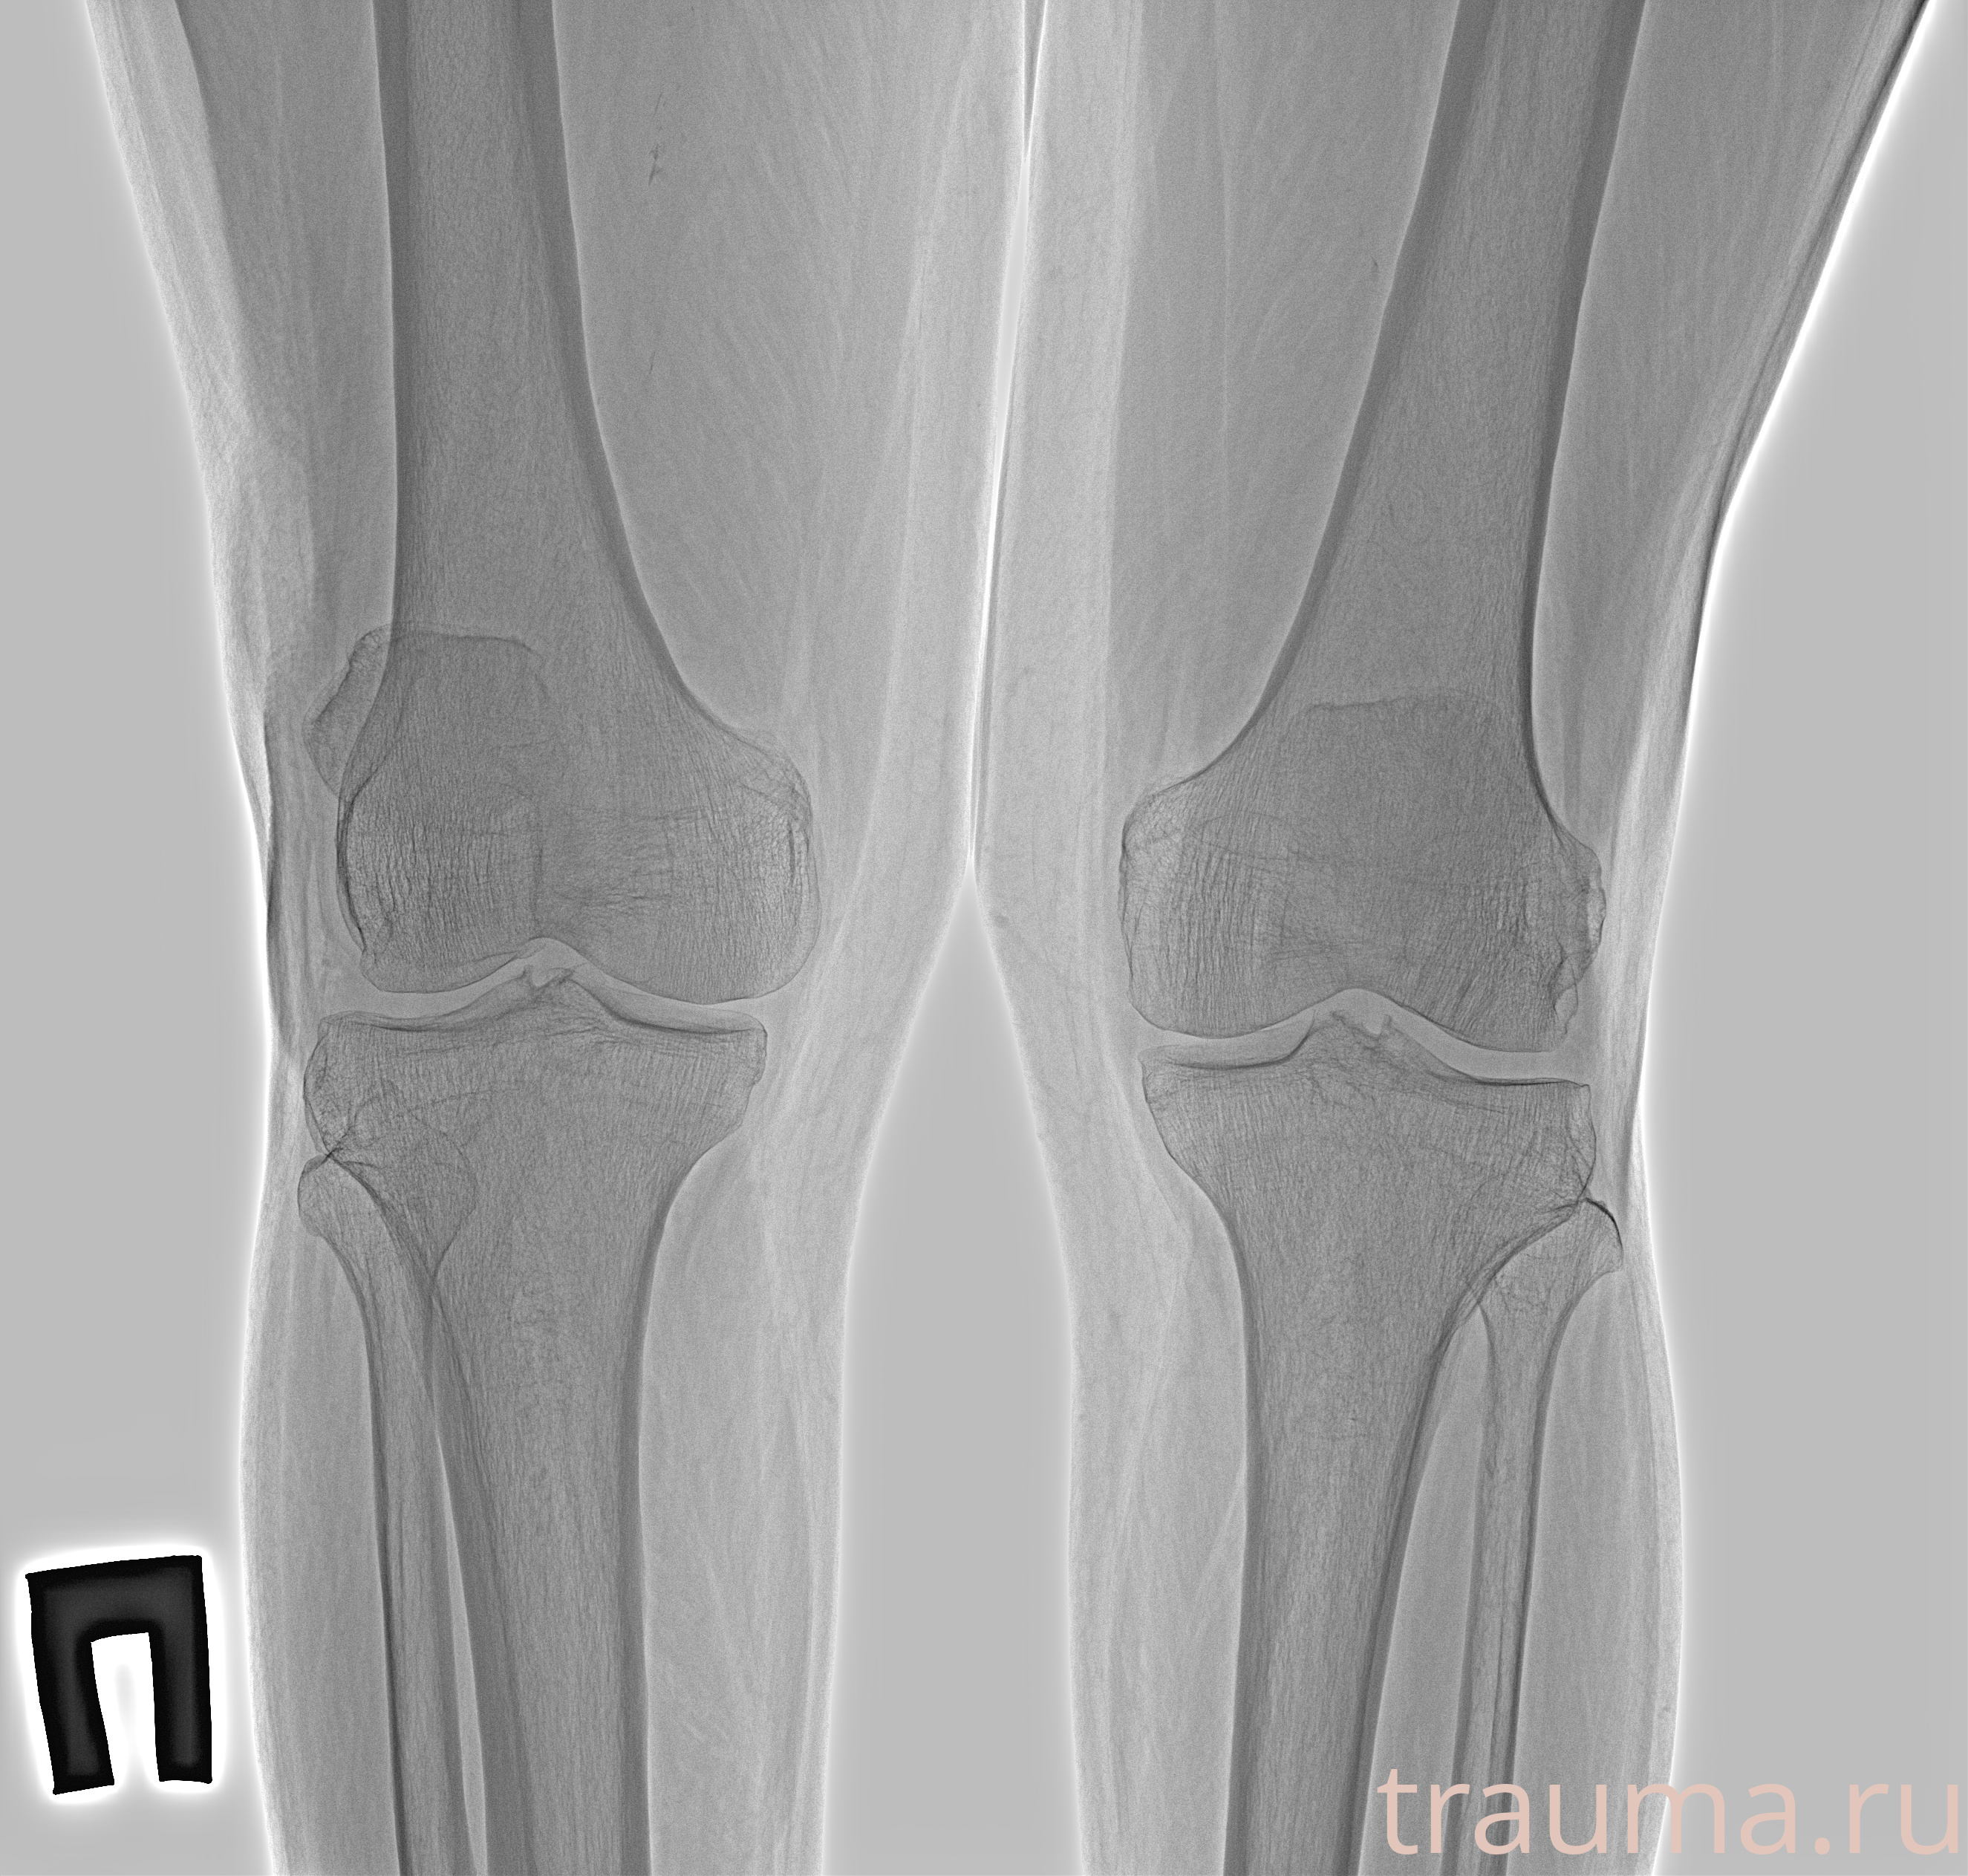

Рентгенограммы